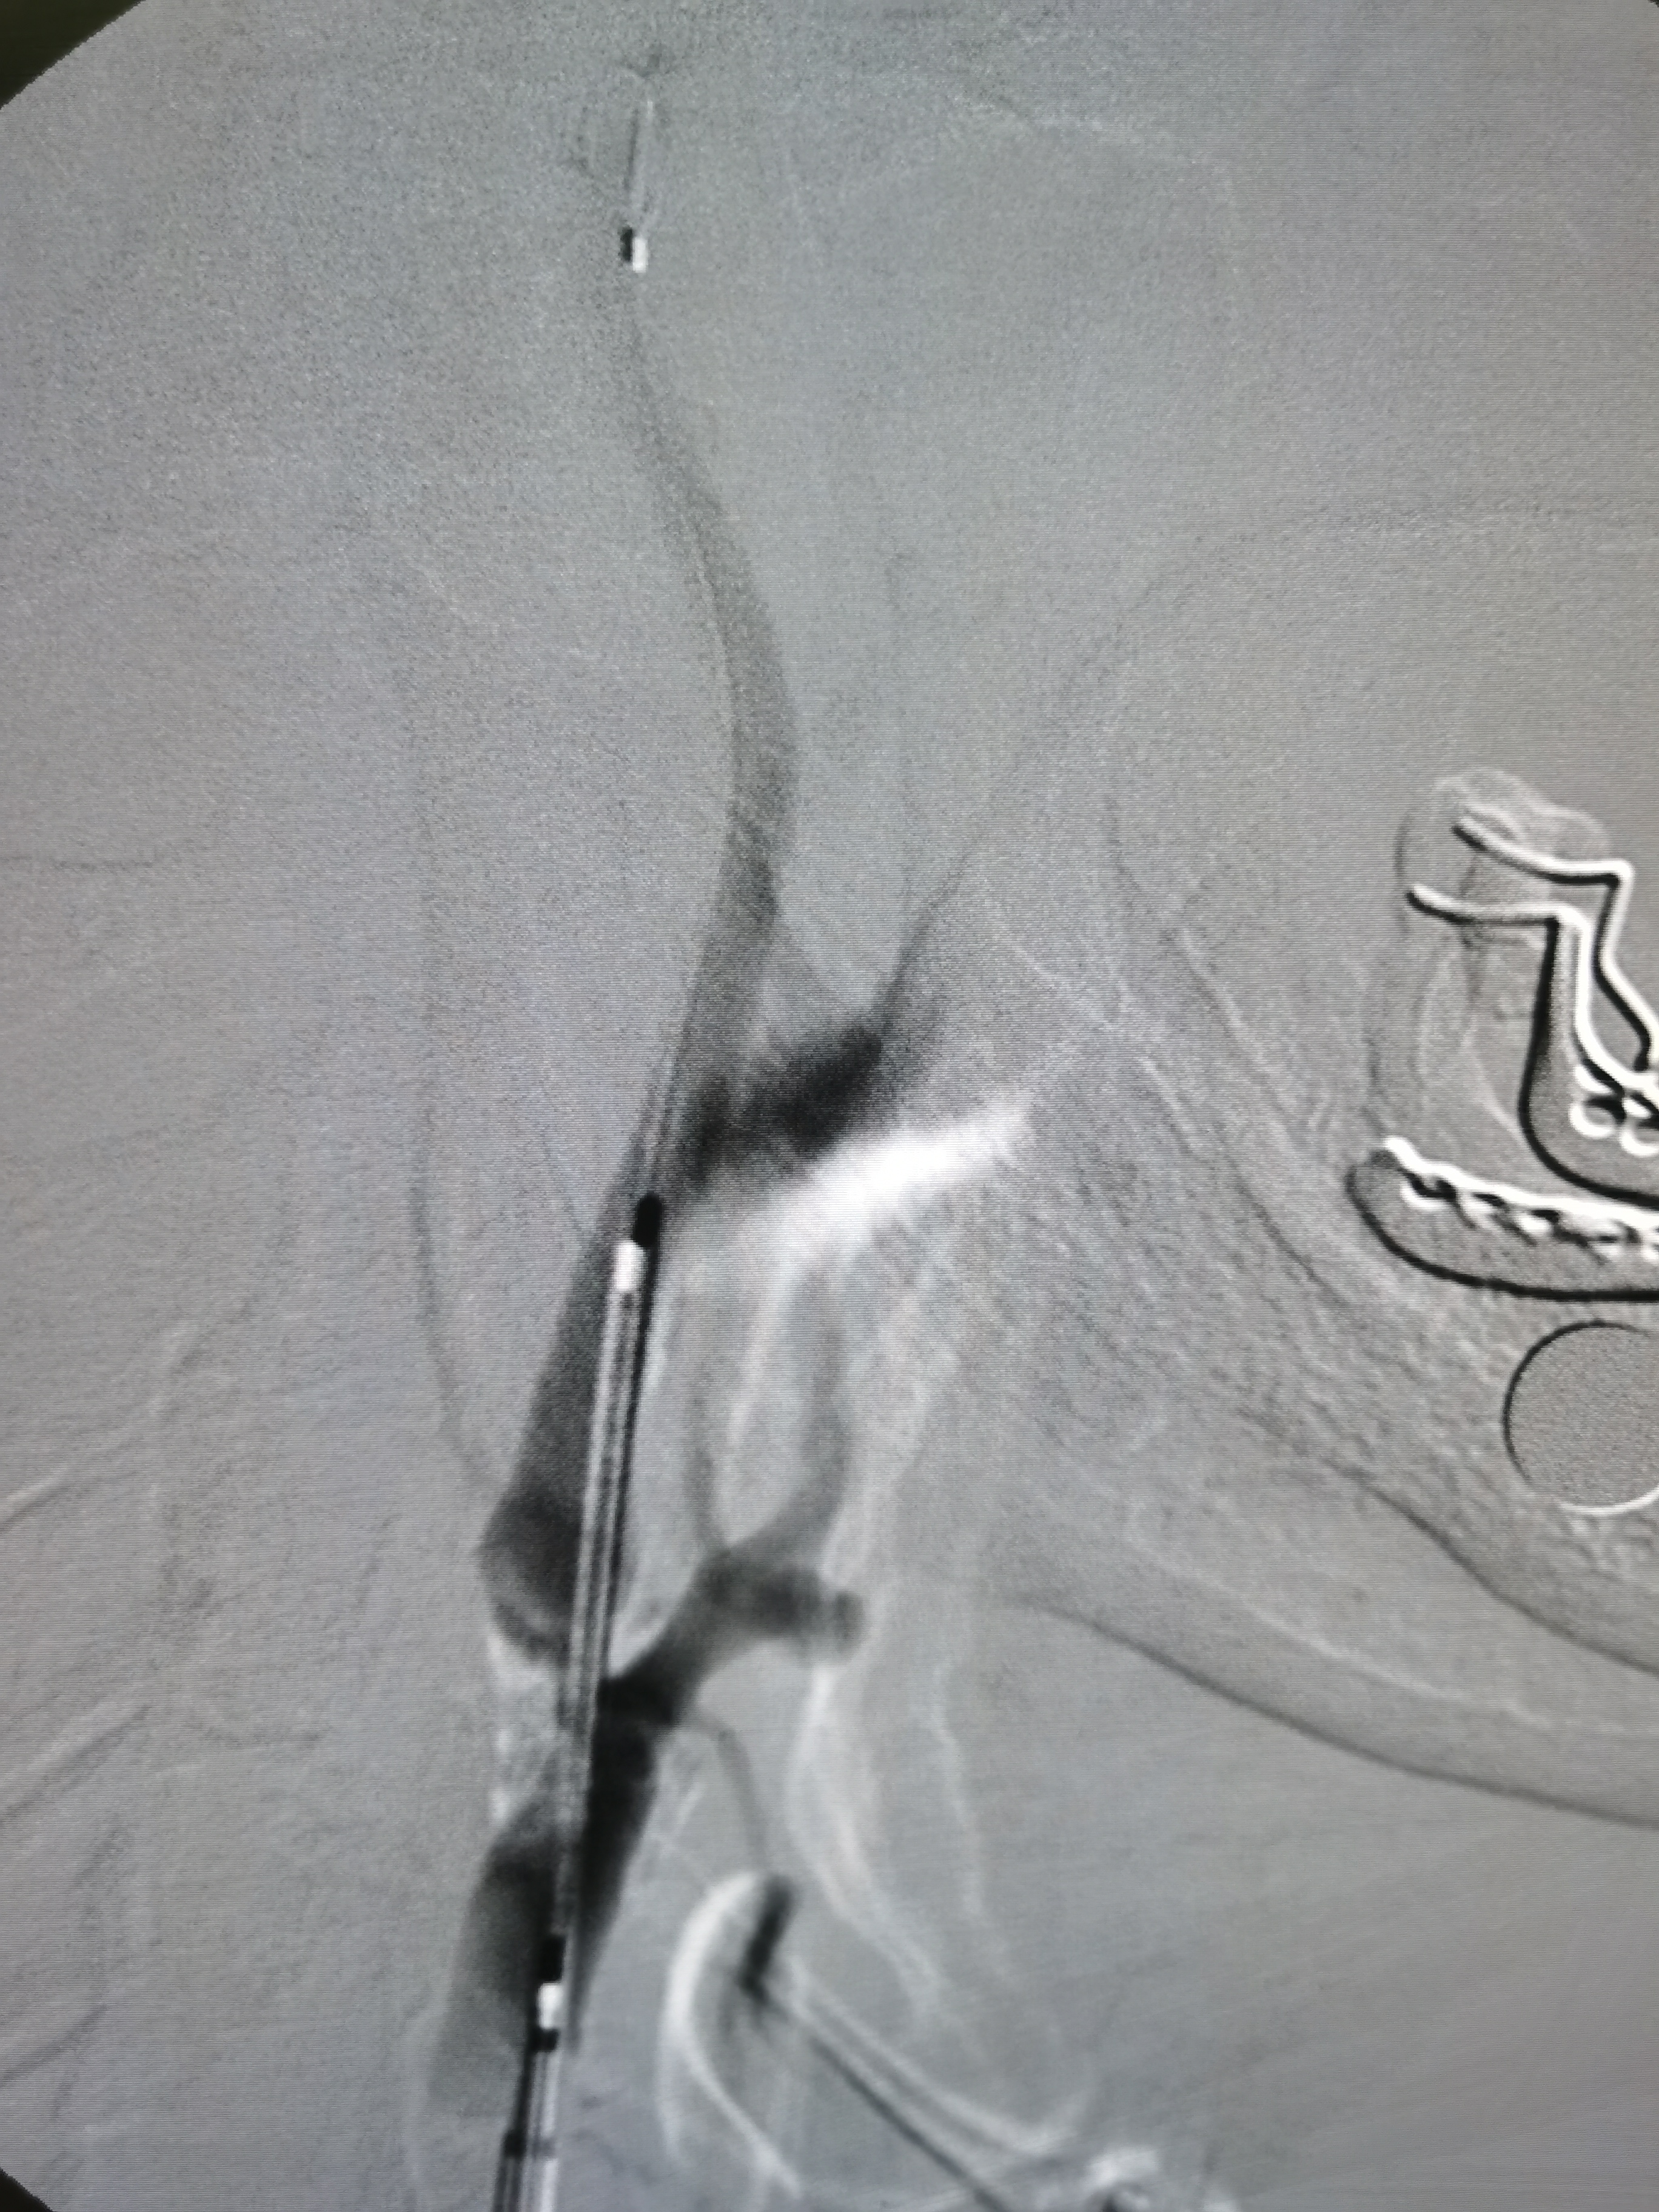

5.0/15支架定位

支架释放后狭窄解除

将导引导管调至右侧颈总末端,送入远端保护伞,4/30球囊预扩。

7-9/40支架定位

支架释放后狭窄改善,考虑患者高龄,颅内动脉硬化,担心术后高灌注出血,遂未再进行大球囊后扩。

撤出保护伞,造影见狭窄改善明显。